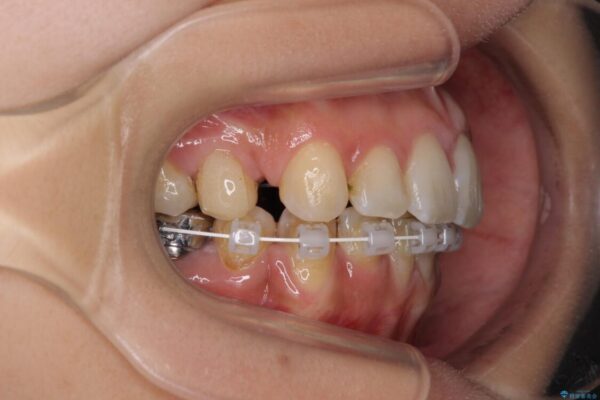

治療途中

• デコボコと口元の突出感 ハーフリンガルでの抜歯矯正 治療途中画像